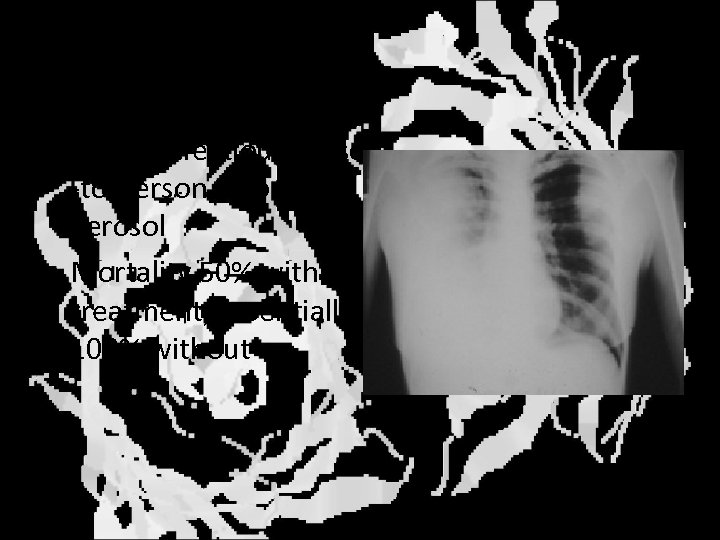

Inhalation anthrax • Inhalation of spores • High lethality even with treatment • Frequently leads to meningitis Characteristic widening of mediastinum

Pneumonic plague • Highly infectious person -to-person through aerosol • Mortality 50% with treatment, essentially 100% without